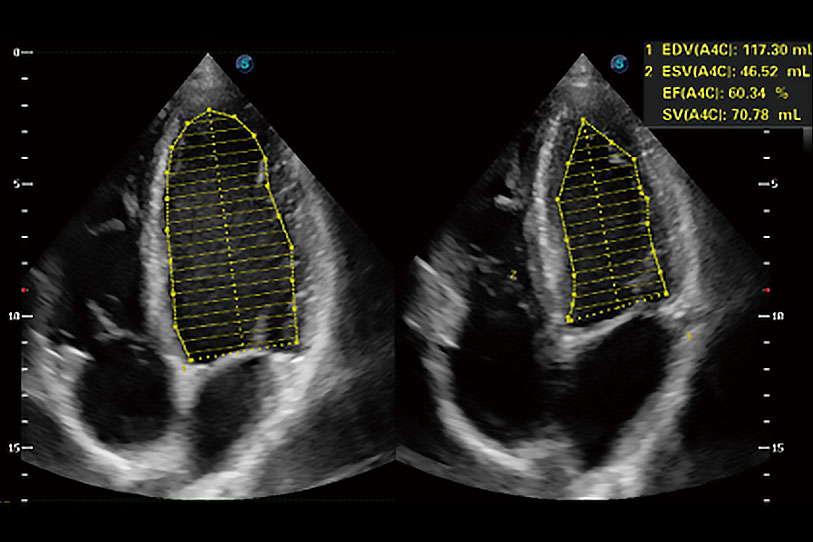

能夠基于左心室壁追蹤和辛普森法,自動計(jì)算射血分?jǐn)?shù),支持多個(gè)可移動點(diǎn)描跡,與手動測量相比,極大節(jié)省了動物醫(yī)生的時(shí)間和精力。

ProPet 70專為動物醫(yī)生設(shè)計(jì),對不同的動物體型和生理結(jié)構(gòu)作出了針對性的優(yōu)化。通過動物影像專用軟件,可滿足個(gè)性化的應(yīng)用需求,幫助動物醫(yī)生獲得更精確的診斷數(shù)據(jù)。